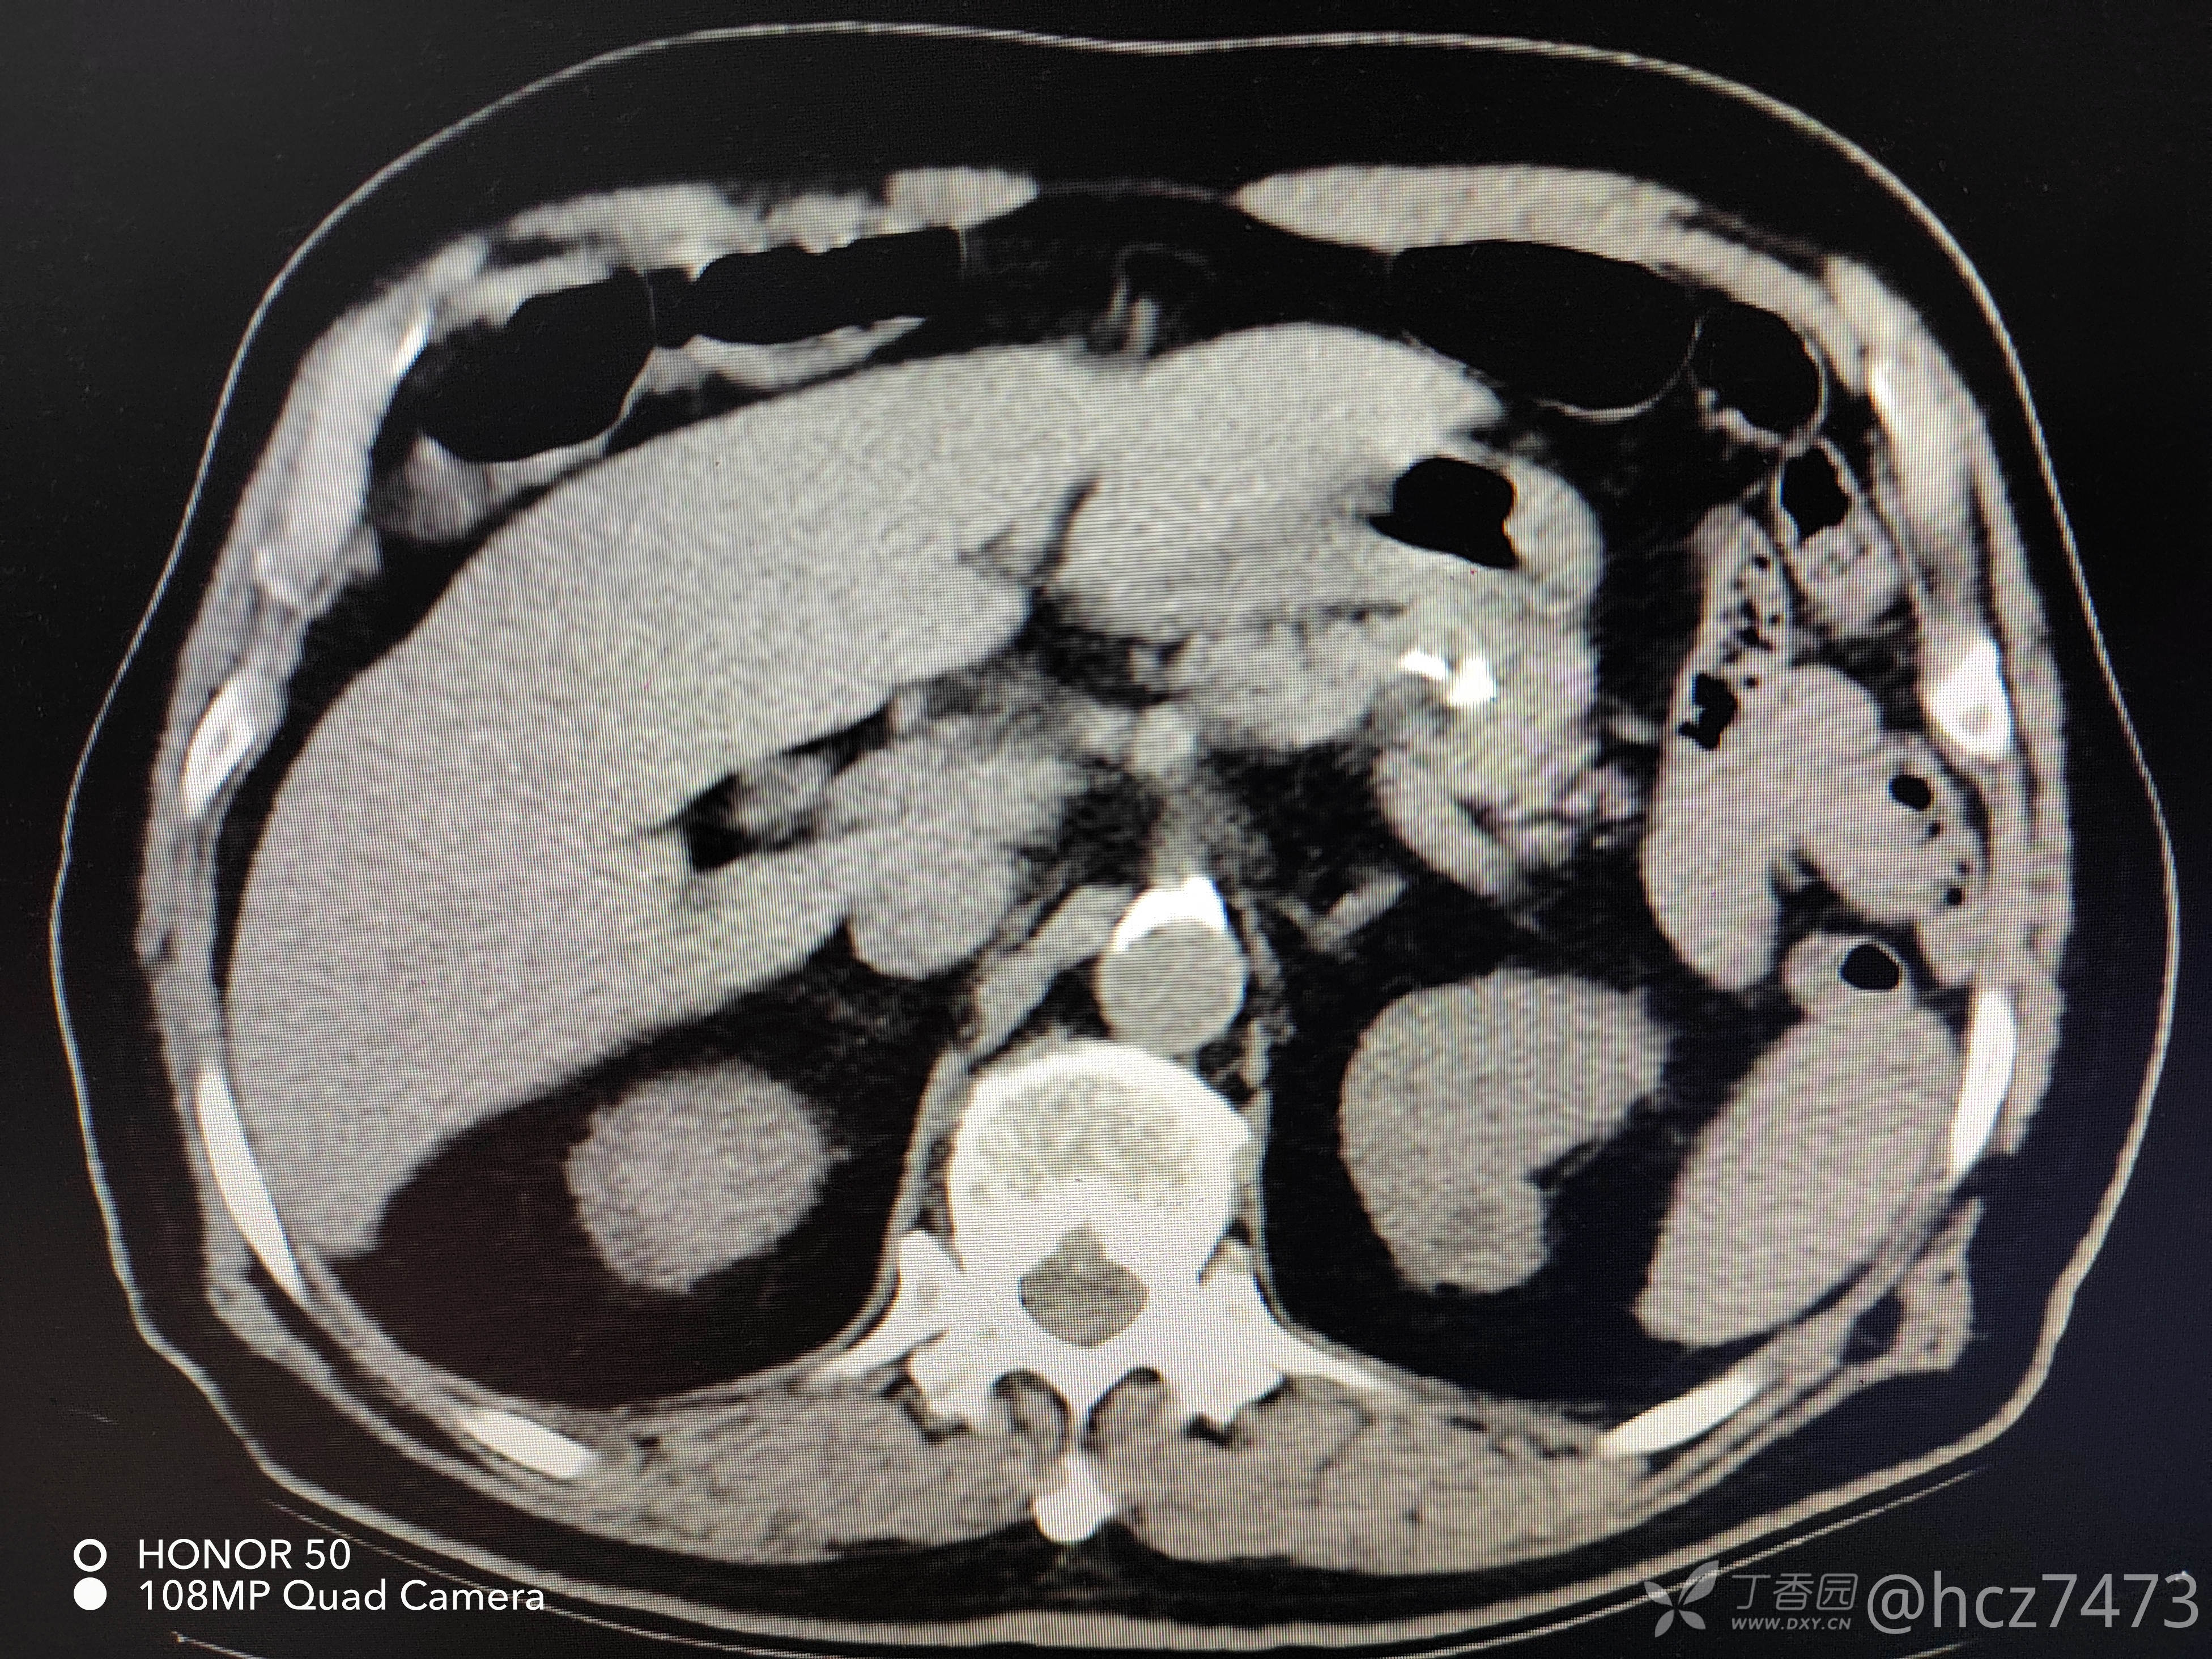

2022.05.12 我院腹盆腔CT检查:

CT报告:胃底部类圆形等密度影,肝左叶内低密度影,胰腺钙化灶,脾脏点状稍高密度影,左肾低密度影,膀胱后壁轻度增厚,前列腺增生。